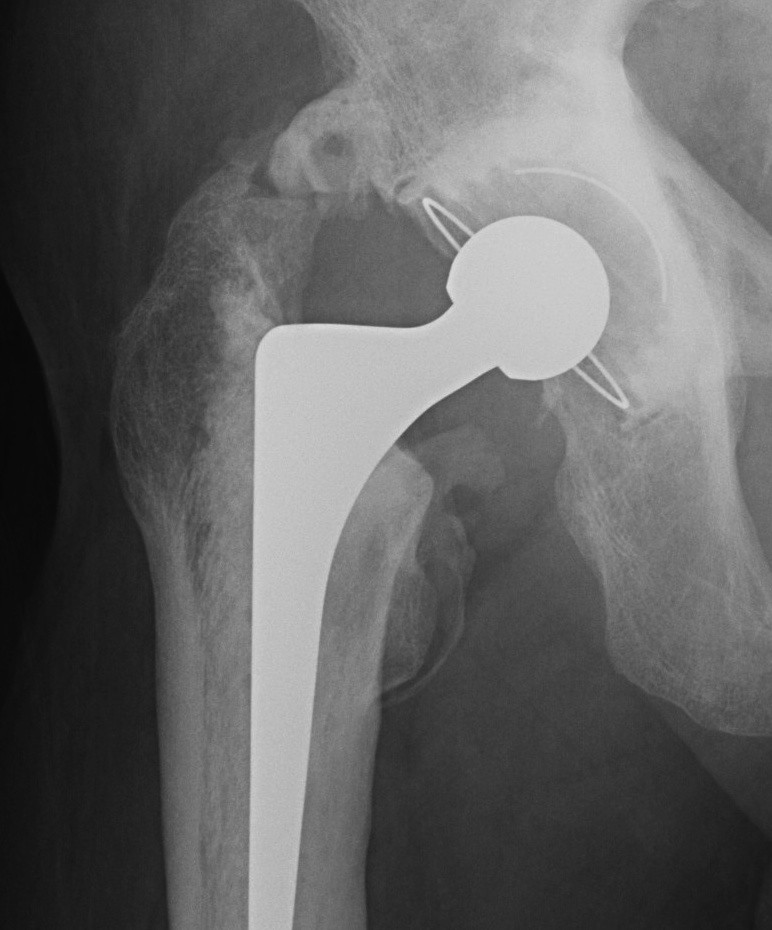

:max_bytes(150000):strip_icc()/x-ray-illustration-of-hip-replacement-1254389829-281a949198324333972a407cc2e90760.jpg)